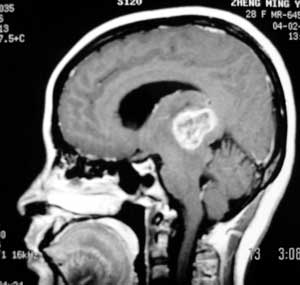

女性,28岁。头痛请会诊

右侧丘脑类圆形等t1,长t2病灶,t1增强明显强化。

t1等信号内出现点状高信号,考虑为出血灶,肿块内侧可见弧形低信号,为脑积液影。长t2,其内有混杂信号,周壁强化明显,内不规则强化,生长位置似在右侧丘脑,又似在来源于侧脑室,故脉络丛乳头状瘤不排外。

考虑1丘脑胶质瘤可能。2室管膜瘤待排。其他可能不完全除外。